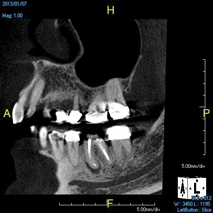

(8.) An original finding of a small lesion on the mesial root of tooth No. 30 was not accompanied by any outward symptoms; therefore, the patient delayed pursuing treatment. When a follow-up CBCT scan was acquired 6 years later, the easy-to-visualize increase in the dimensions of the lesion motivated the patient to elect a treatment plan.

Figure 8

(9.) An original finding of a small lesion on the mesial root of tooth No. 30 was not accompanied by any outward symptoms; therefore, the patient delayed pursuing treatment. When a follow-up CBCT scan was acquired 6 years later, the easy-to-visualize increase in the dimensions of the lesion motivated the patient to elect a treatment plan.

Figure 9

Identifying the shape and location of the roots of teeth to be removed is critical to performing safe exodontia. Some clinicians virtually deconstruct teeth using CBCT images prior to actually sectioning and removing them. Being able to recognize pathoses and differentiate affected structures from normal structures is key in deciding what the treatment should be and when that treatment should be initiated (Figure 8 through Figure 10). The arena of the oral surgeon is larger than that of many general practitioners, involving the sinuses and condyles and other considerations in and around the entire mandible and maxilla. Certain fractures and other conditions that some general practitioners feel uncomfortable treating are often referred for evaluation and treatment by an oral surgeon. Because of this, oral surgeons require the most accurate and complete diagnostic information available. The American Academy of Oral and Maxillofacial Radiology recommends that "cross-sectional imaging be used for the assessment of all dental implant sites" and has stated that "CBCT is the imaging method of choice for gaining this information."18